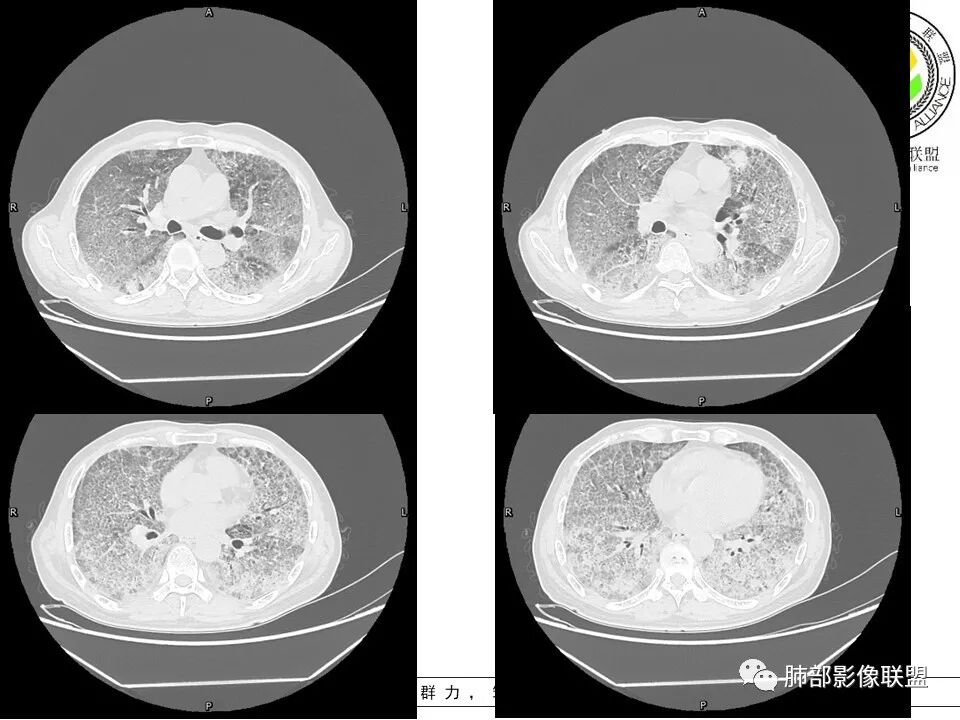

上肺为主小叶中心型肺气肿——吸烟

碎石路征,下肺为主

肺部结节

左上叶斑片状高密度影

肺血坠积

1、PAP符不符合?

2、多发结节:是否存在尘肺?

3、左上叶斑片状高密度影:感染?肿瘤?

4、双侧小叶间隔增厚:是否考虑CA?

PAP应该有

结节如何解释?

感染也应该有

双侧小叶间隔增厚、对称

南边:只有GGO+网格(小叶间隔增厚),然后就是分布的问题

1、GGO+网格——碎石路征

2、分布无特定位置,较随机

3、可有少许实变——部分与层厚有关

4、小叶间隔内静脉增粗

5、病灶较多时部分可见重力趋势

1.由于脂蛋白的沉积和占据,肺泡腔含气量减少,这是影像上较大范围“磨玻璃影”的基础。

2.由液体、细胞浸润和纤维组织造成的小叶间隔增厚是影像上多边形“铺路石征”的基础。

3.显眼的小叶间隔对病灶有阻挡作用是形成影像上“地图样改变”的基础。我们观察到的病灶与临近相对正常肺组织之间常常有比较清楚的分界。

这种表现颇具特征性。但有部分患者(1/4)仅有磨玻璃影而未显示小叶间隔增厚,这种情形我们很难将PAP列为第一诊断。

4.病灶常多发,但心尖区及膈角区相对轻微。

5.部分病例显示有局部实变影